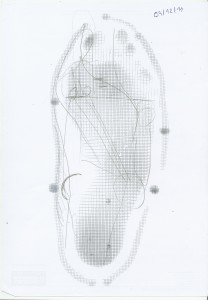

Après mon premier marathon pieds nus.

Il se trouve que j’ai été contacté dernièrement par l’Institut National de Podologie (Paris) pour les aider à trouver des coureurs expérimenté.e.s pour une étude comparative de foulée pieds nus / amortie. Ce heureux hasard fait qu’il y a une quelques semaines, j’ai passé deux heures à trottiner sous les yeux froids et impartiaux de plusieurs machines capables de quantifier les nuances de la course humaine. Ainsi, j’ai pu récupérer quelques données que j’ai pu faire commenter par un professionnel de la santé (podologue de sport) dans cet article « Analyse podologue foulée barefoot« . Je vais laisser les professionnels commenter les changements morphologiques – il me manque les connaissances requises, et le vocabulaire spécifique.

Ce qui saut aux yeux, ce sont deux choses : pieds nus l’appui du pied est très bien distribué entre l’avant, le milieu et l’arrière du pied. Ensuite, les orteils … ne jouent aucun rôle dans les différentes phases d’attaque. Les trois premiers métatarses engrangent presque toute la charge à l’avant du pied. Le talon est sollicité, mais pas plus que les autres parties du pied.

Voici comment mes pieds attaque le sol. On mesure ici la pression (Newtons/centimètre carré) à 14 km/h à travers le pied. Je trouve (c’est quantitatif, hein ;-)) que l’impact se dispatche remarquablement bien entre les deux niveaux d’interférence entre le pied et le sol. Je pose clairement le talon, mais le plus gros de l’impact est sur le devant du pied. Bien ça.